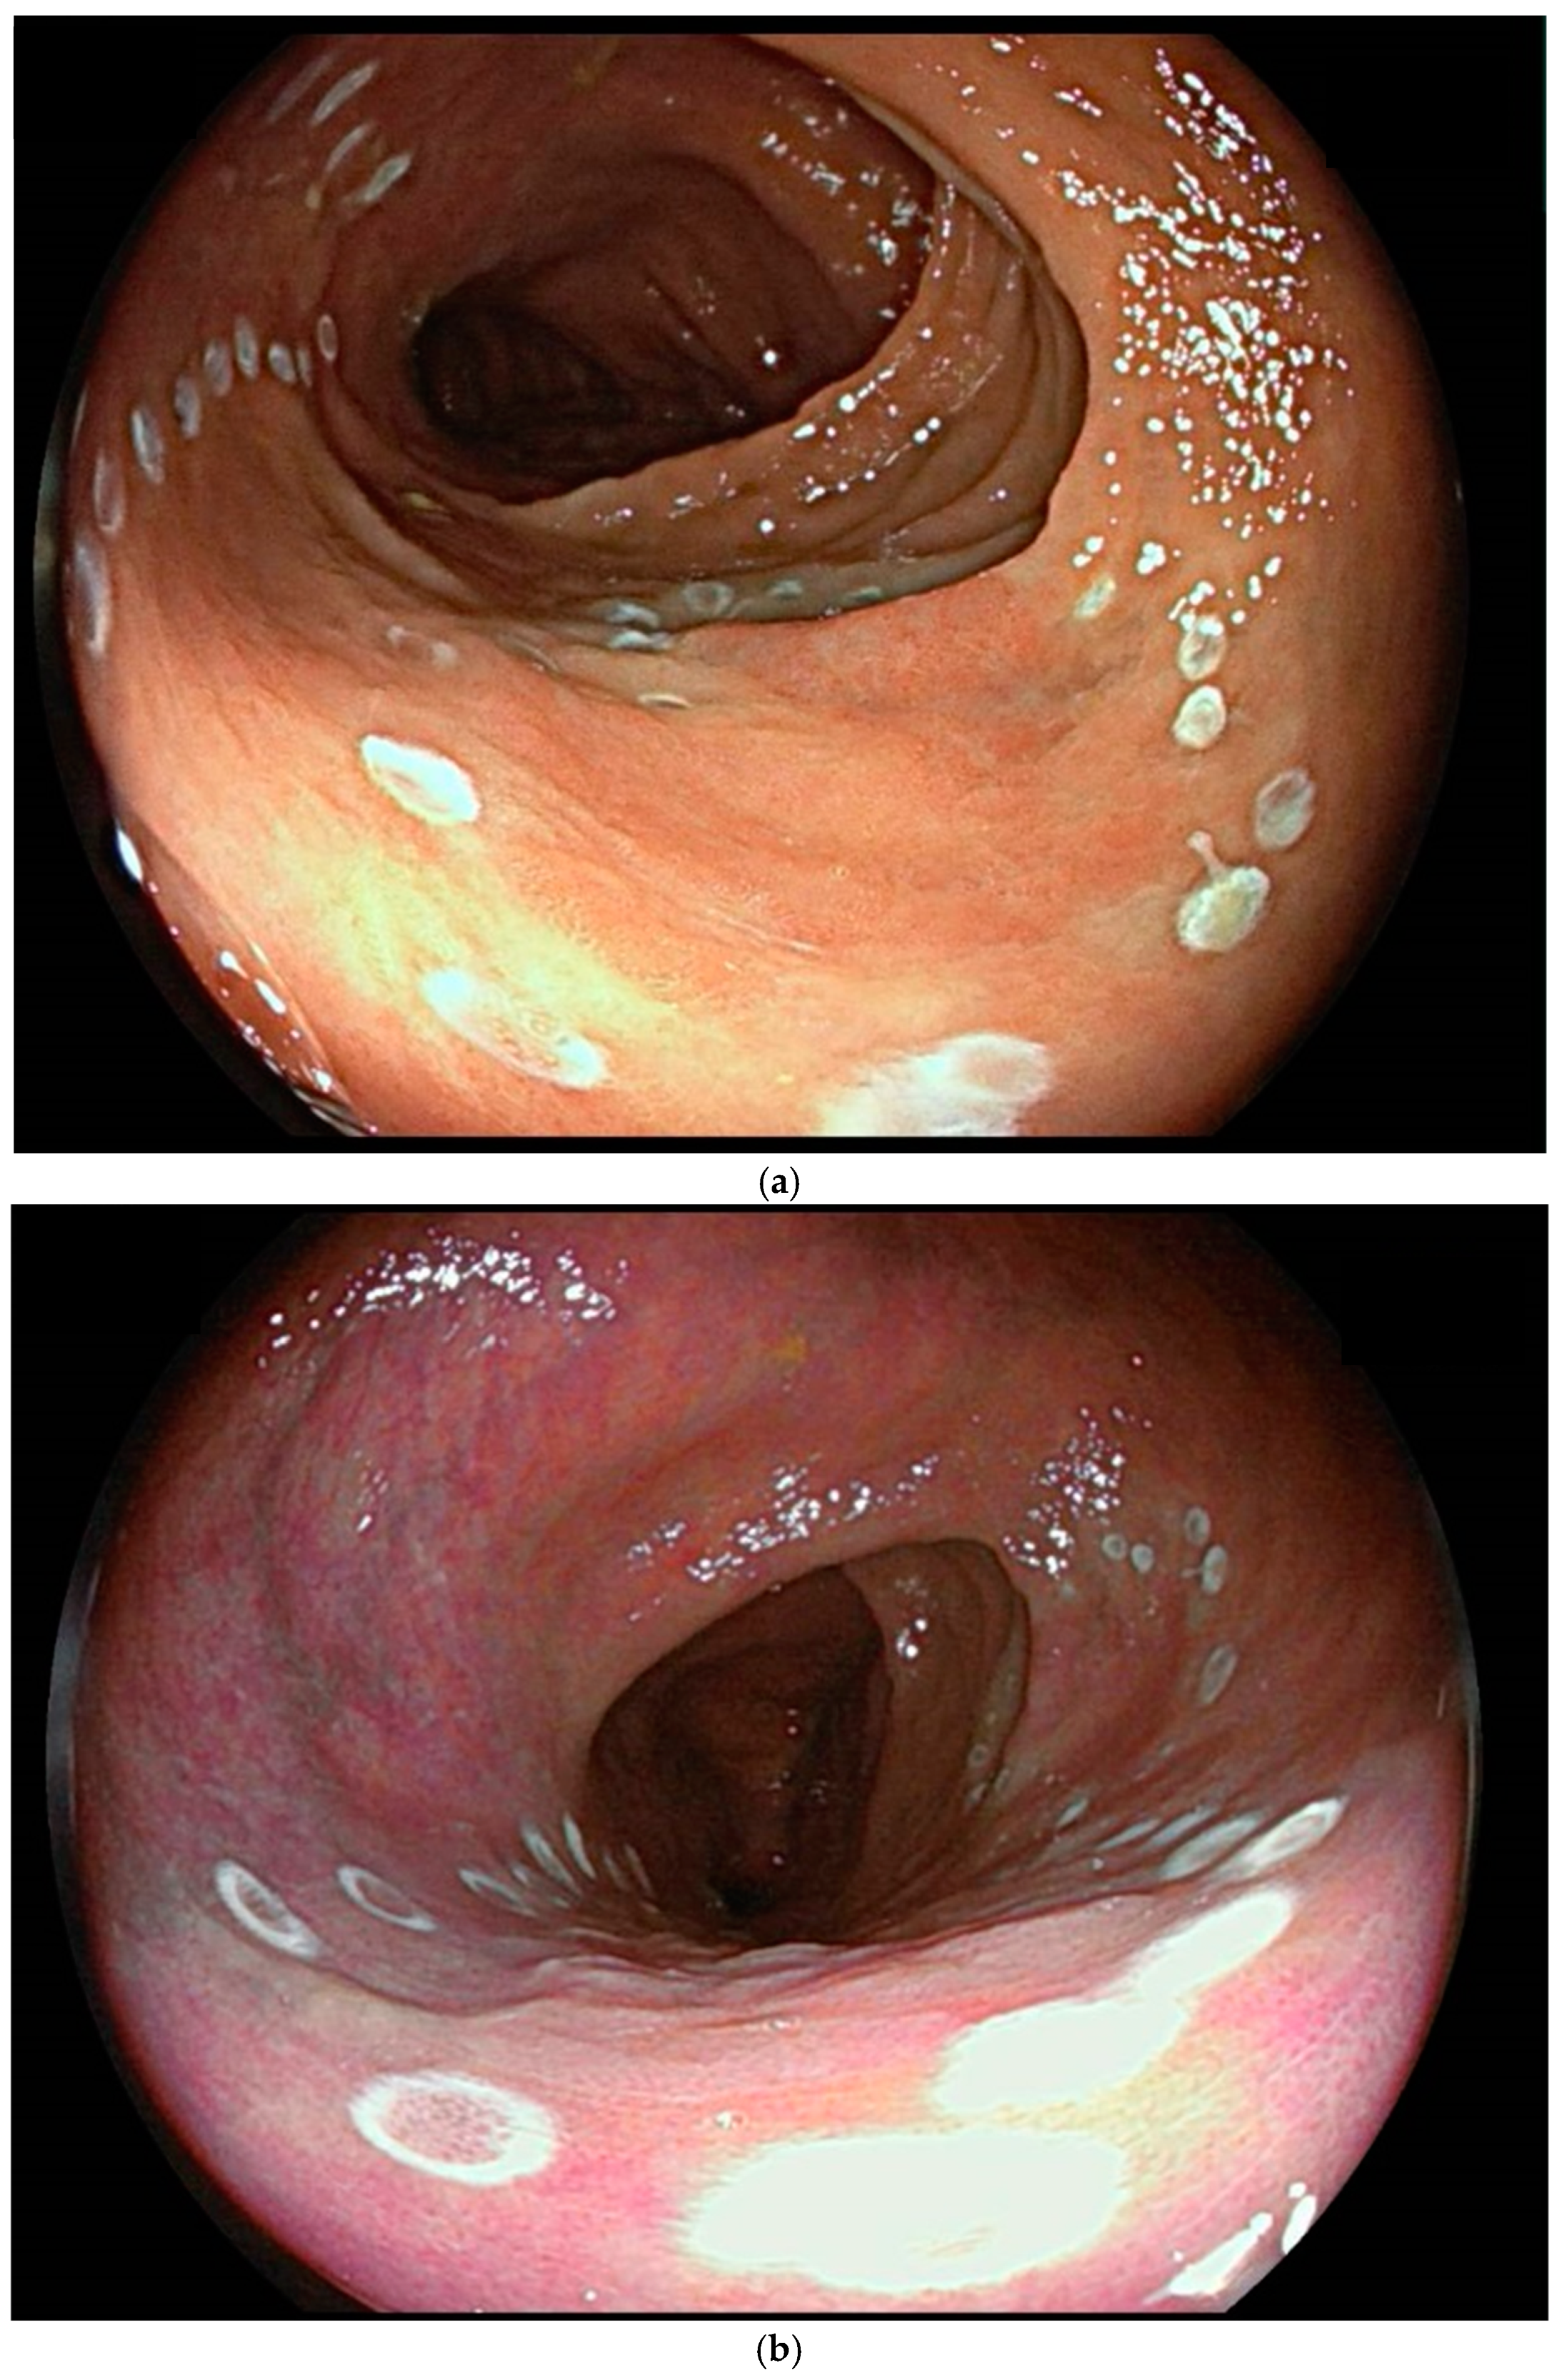

5. Surveillance

7. Endoscopic Assessment